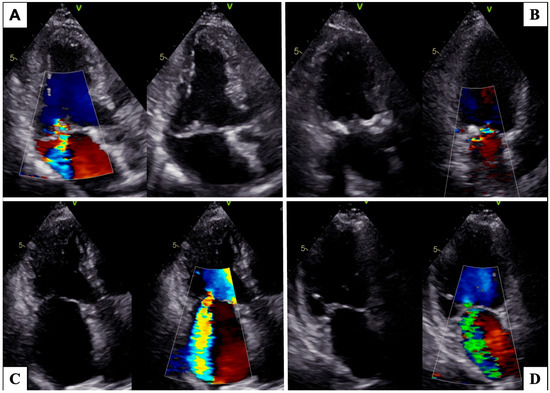

3.2. Multimodality Imaging in MR Assessment

- Goebel, B.; Heck, R.; Hamadanchi, A.; Otto, S.; Doenst, T.; Jung, C.; Lauten, A.; Figulla, H.R.; Schulze, P.C.; Poerner, T.C. Vena contracta area for severity grading in functional and degenerative mitral regurgitation: A transoesophageal 3D colour Doppler analysis in 500 patients. Eur. Heart J.-Cardiovasc. Imaging 2018, 19, 639–646. [Google Scholar] [CrossRef]